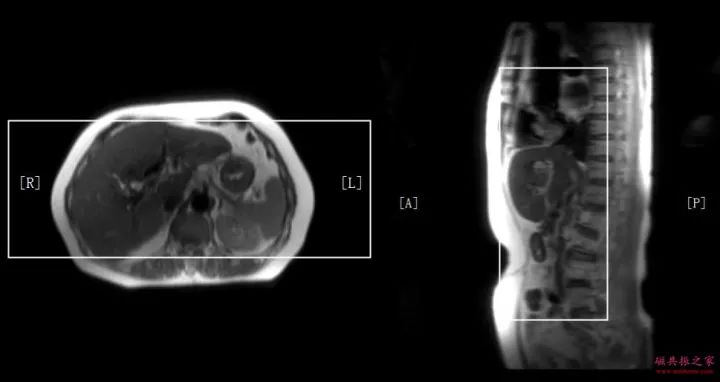

冠状面:冠状面稳态自由进动序列/单次激发T2WI序列。

在横轴位和矢状位定位,扫描范围包括肝脏前后缘,合理调整扫描范围,需包括整个病变范围。

上腹部的扫描应首先扫描范围较大的冠状面图像,以便对病变及周围组织器官作出大体地评估,更有利于精准地定位和扫描方案的制定。